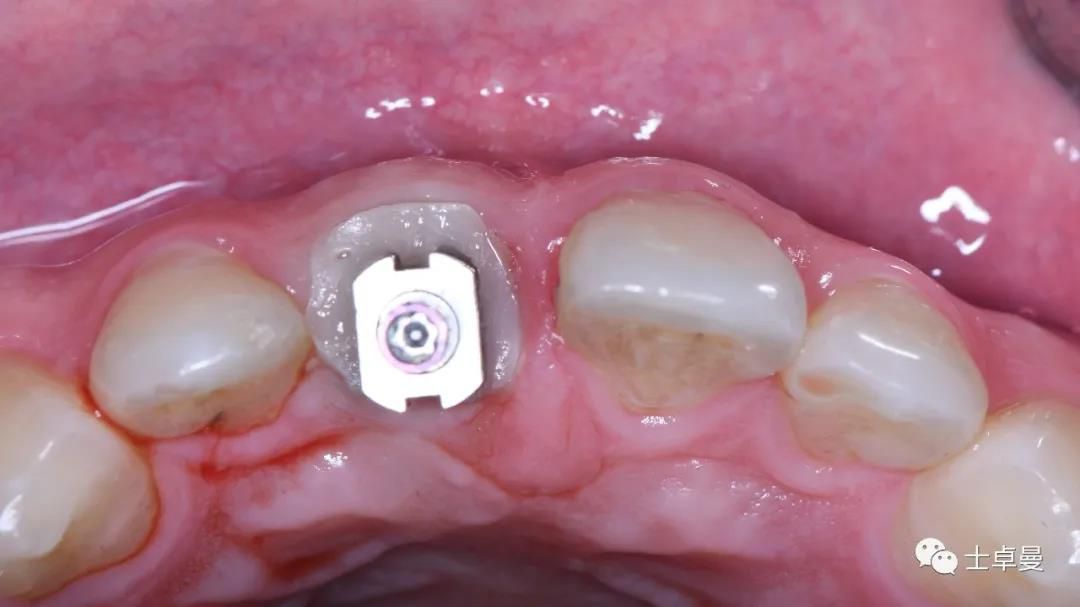

分根

拔出腭侧牙根

保留唇侧牙片

牙周探针探查牙片位置及松动度

就位种植外科导板

指示杆观察备孔三维位置

种植体植入后,植体唇侧间隙内填塞骨粉0.25g,胶原骨100mg,安放愈合帽,明胶海绵暂时封闭创面

术后即刻CT示,种植体植入位置理想

术后即刻制作个性化愈合帽

上部制作马里兰桥临时修复体